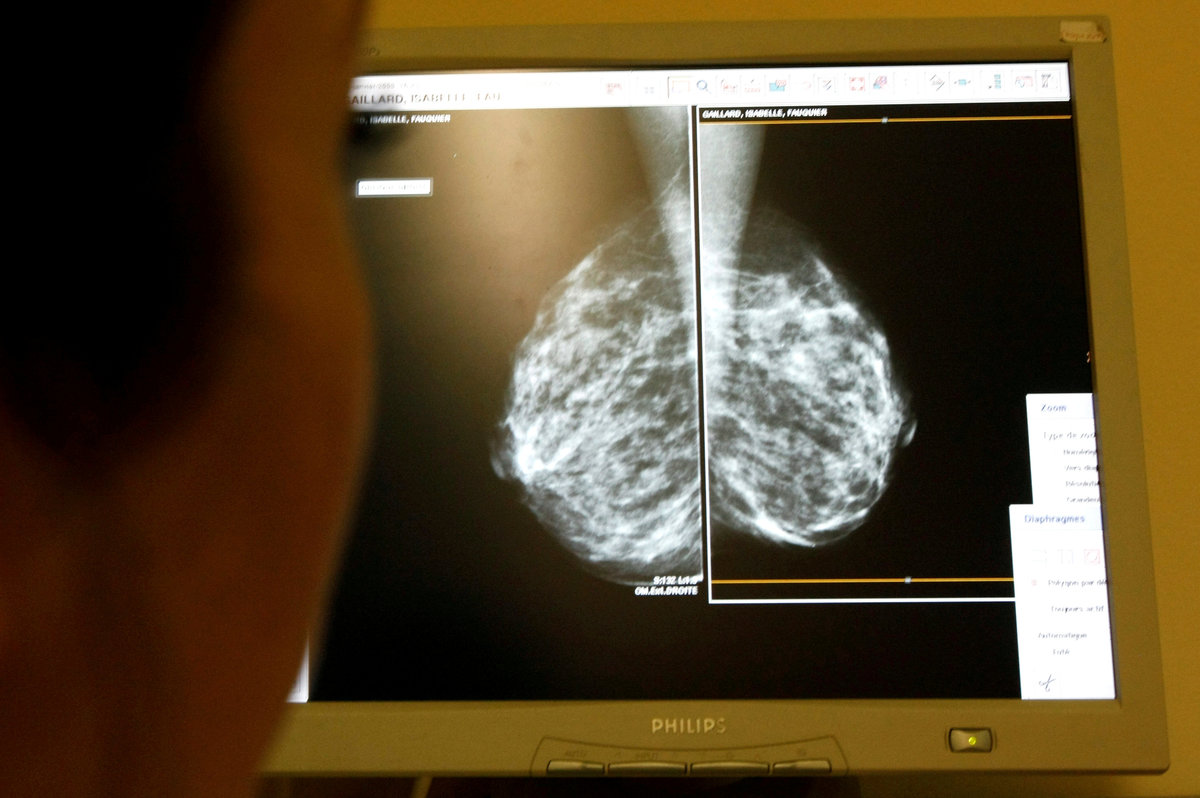

The research, presented at the American Society of Clinical Oncology (ASCO) meeting in Chicago, studied how to treat women with early-stage breast cancer that responds to hormone therapy.

The study, dubbed TAILORx, was also published in the New England Journal of Medicine. It involved more than 10,000 women with breast cancer that had not spread to nearby lymph nodes and whose tumors respond to hormone therapy and test negative for the HER2 gene.